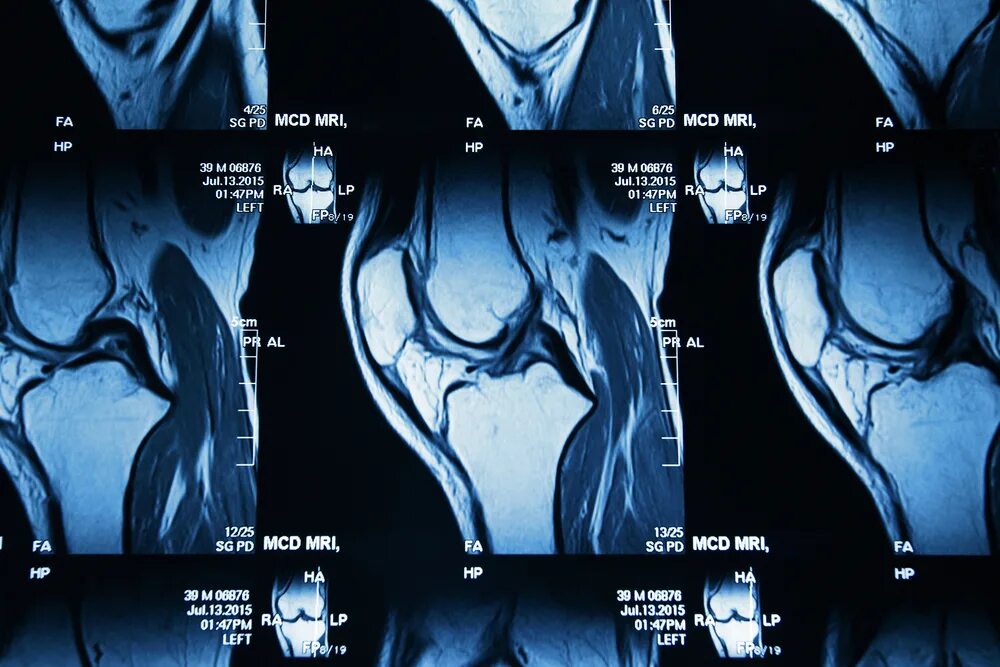

Мрт коленного сустава одежда